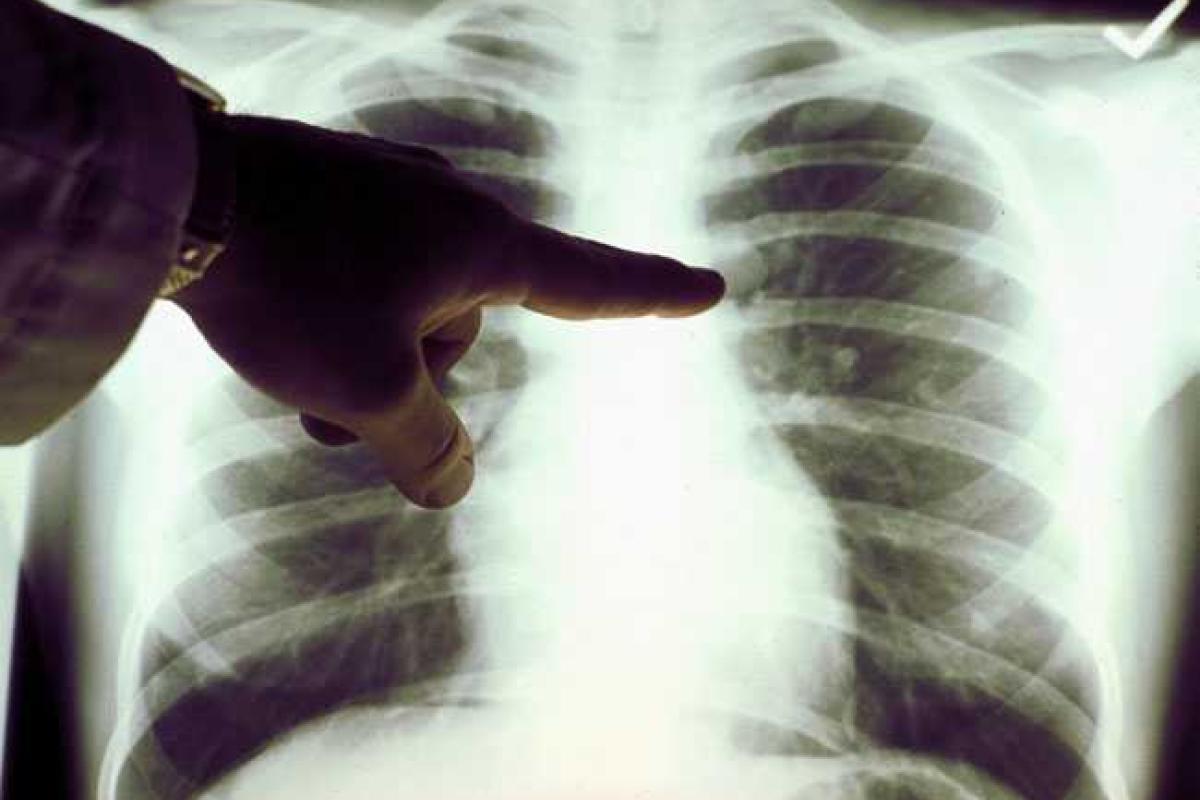

Рак легких – одна из самых распространенных форм онкологического заболевания во множестве развитых мировых странах. Злокачественный процесс центрального рака легких, локализующийся в основном в бронхах, по смертности отстает только от сердечно-сосудистых заболеваний.

Остальные симптомы зачастую появляются от распространения метастазов – передвижения раковых клеток к другим органам по сосудам. Авторитетные онкологи отделения клиники Топ Ихилов проводят эффективную диагностику и лечение рака легких в Израиле, применяя наиболее инновационные способы и современную медицинскую аппаратуру.